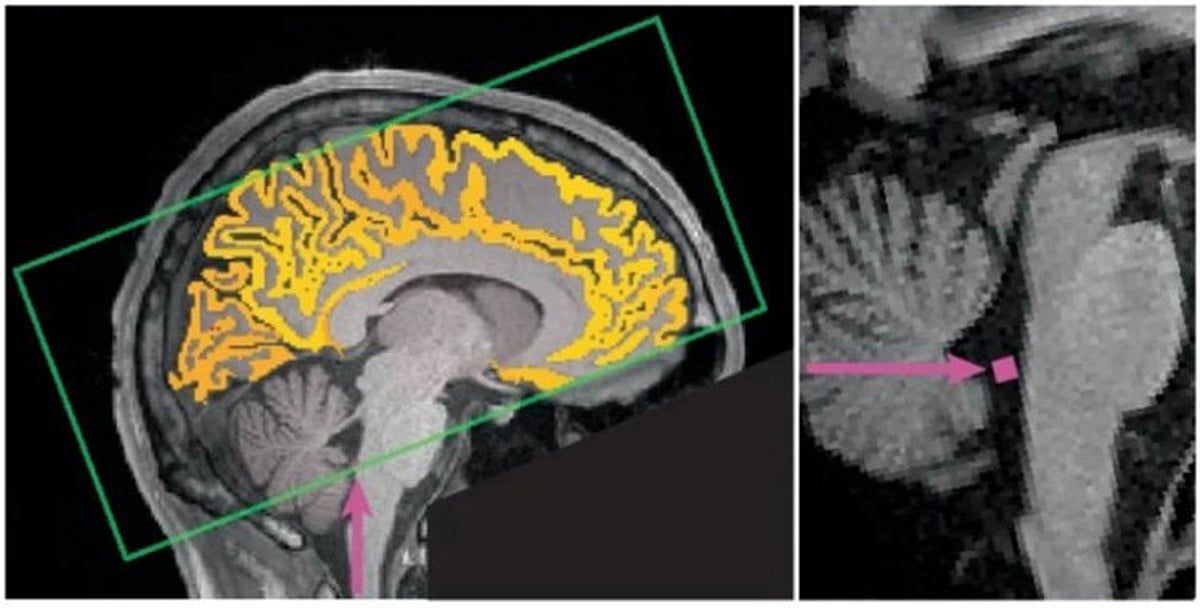

وأوضح "باهمام" في تدوينة عبر حسابه على منصة إكس، أنه عند قلة النوم تظهر لدى الإنسان فترات من ضعف الانتباه والتركيز، وخلالها يقوم الدماغ بدفع السائل الدماغي الشوكي إلى الخارج في محاولةٍ للتخلص من السموم، وهي عملية تحدث عادة أثناء النوم فقط.